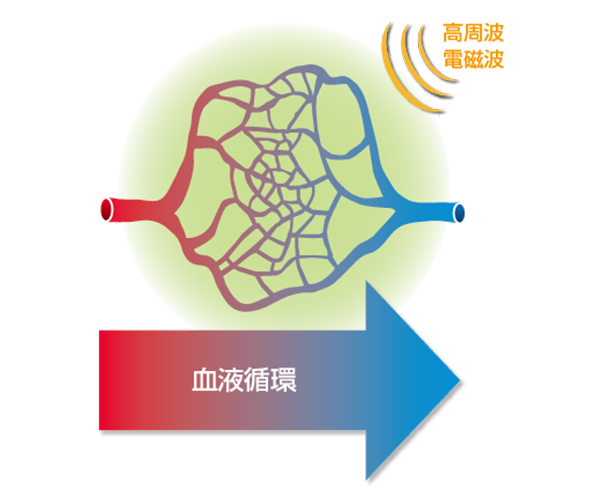

マイクロ波発生装置(SHT)は2.45GHz、出力300-700Wで43℃まで体温を上げてガン細胞の周辺の血管を破壊して縮小させ、健常な細胞を活性化します。

マグシャワーは1台800ガウスの磁力で、血液を電荷して隅々まで循環させます。

どちらも体温を上げ血流を良くして、本来体が持つ免疫力向上を促します。

どんな治療ができるの?

5cmまでのがん、リウマチ、パーキンソン病、筋肉痛、関節痛、凝り症、脳性マヒ、子宮・卵巣の病気、狭窄症、不眠、冷え性、前立腺肥大など多岐にわたって効果が実証されています。あきらめずにご相談下さい。

マグシャワーの血流への作用は筋肉への酸素、栄養の運搬能力を向上させますので、スポーツ等のパフォーマンス向上が期待できます。